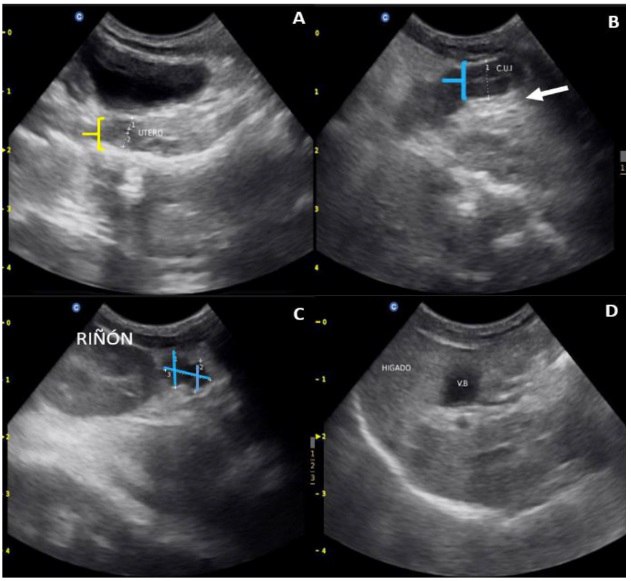

Ультразвуковые находки у самки суриката перед операцией (отечная матка, левый яичник с кистами, повышенная эхогенность печени)

Узловые образования (лютеома) в левом яичнике суриката, выявленные во время операции